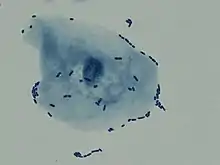

![]() | |

| Multiple white cells seen in the urine of a person with a urinary tract infection using microscopy | |